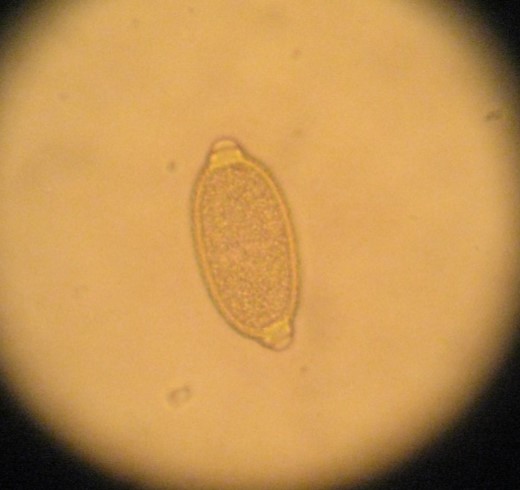

Œuf de capillaire, caractéristique en forme de citron avec à chaque extrémité

des bouchons polaires plats - Crédit photo : Minh Huynh, Nacologie©